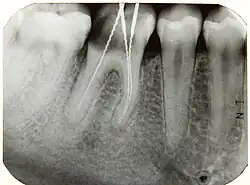

Die röntgenologische Längenbestimmung ist eine zahnmedizinische Technik zur Bestimmung der Wurzelkanallänge während einer Wurzelkanalbehandlung.

Hierbei wird eine Röntgenaufnahme des zu behandelnden Zahnes angefertigt, während sich in diesem ein röntgendichter Gegenstand befindet, beispielsweise eine Hedströmfeile oder ein Silberstift, der bis zur vermuteten beziehungsweise taktil gefundenen Arbeitslänge eingeführt wurde. Auf diese Weise kann die Übereinstimmung der vermuteten Arbeitslänge mit der röntgenologischen Wurzelspitze bestimmt werden, die jedoch aufgrund der Projektion einer dreidimensionalen Struktur in eine zweidimensionale Ebene nicht zwingend mit der anatomischen Wurzelspitze übereinstimmen muss. Der endodontische Apex (auch physiologischer Apex), eine Einziehung der Pulpa, liegt ca. 1–2 mm vor (coronal) dem anatomischen Apex.[1]

Aufgrund des aus dem Wurzelkanal herausragenden Instrumentes sowie dem bei der Wurzelkanalbehandlung oft verwendeten Kofferdams kann eine Röntgenaufnahme nicht in Paralleltechnik angefertigt werden, die einen Aufbiss des darzustellenden Zahnes auf den Filmhalter verlangt. Stattdessen wird auf die Halbwinkeltechnik ausgewichen.